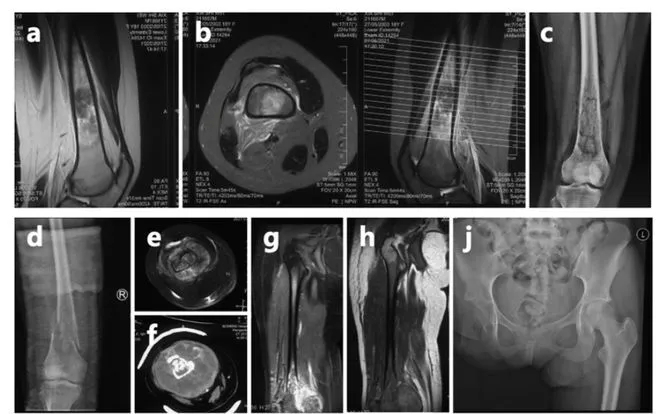

安徽合肥23歲女孩「夏夏」,18歲確診骨癌、19歲截肢,撐過6次重大手術,5年來一路與癌症對抗。她近日再度傳出癌細胞轉移至肋骨與胸膜,需展開新一輪治療。

據《大象新聞》報道,夏夏2019年高考前身體出現異狀,右腿經常劇痛,甚至在數學考試中當場暈倒,送醫檢查後確診為骨癌,祖母求父母帶她去北京就醫。2019年至2021年間,她陸續接受右腿截肢、肺部切除等6次大型手術,對於失去右腿,她還是樂觀面對平靜地表示:「一條腿換一條命,很值得。」

夏夏因癌細胞轉移,在網上公布要切除肋骨和胸骨。

夏夏在高考結束後去醫院,被確診骨癌。

治療期間,夏夏幾乎是獨自承受一切。她透露,父親在她生病後從未探望,母親則在一年後與她斷絕聯繫,甚至直言她是「累贅」。在缺乏家庭支持的情況下,她自己簽署6次手術同意書、存錢購買義肢,輾轉各地求醫。

然而,病情並未就此結束。今年初(2026年),夏夏再度檢查出癌細胞轉移至肋骨與胸膜,目前正在上海瑞金醫院評估治療方案,預計接受新一輪化療、標靶治療及手術。